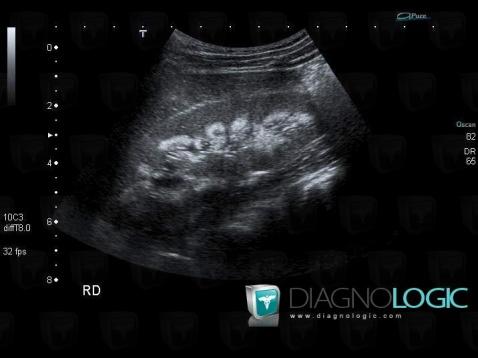

The images below illustrate this case for diagnoses Nephrocalcinosis, for the modalities (US)

Nephrocalcinosis, Kidney, US

Here is the specific information in the key image above:

- Diagnosis Nephrocalcinosis, Location(s) Kidney, with gamuts Hyperechoic renal medulla